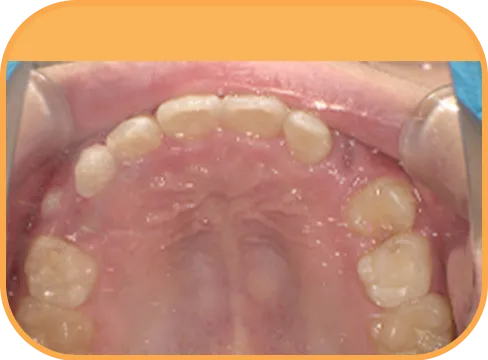

• Before

• 正 面

治療前正面からの歯の様子

• 上 顎

治療前上顎からの歯の様子

• 下 顎

治療前下顎からの歯の様子

• 右 側

治療前右側からの歯の様子

• 左 側

治療前左側からの歯の様子

主 訴

上の前歯がねじれている、ガタガタ

治療内容

インビザライン・ファースト

治療期間

8か月

治療費(税別)

450,000円+診断料50,000円

リスク・副作用

• 親知らずの影響や加齢などによって、凸凹が生じる可能性があります。

• 治療の初期段階では痛みや不快感が生じやすくなりますが、1週間前後で慣れます。

• 顎の成長発育によって、噛み合わせや歯並びが変化する可能性があります。

• 状況により当初予定した治療計画を変更する可能性があります。